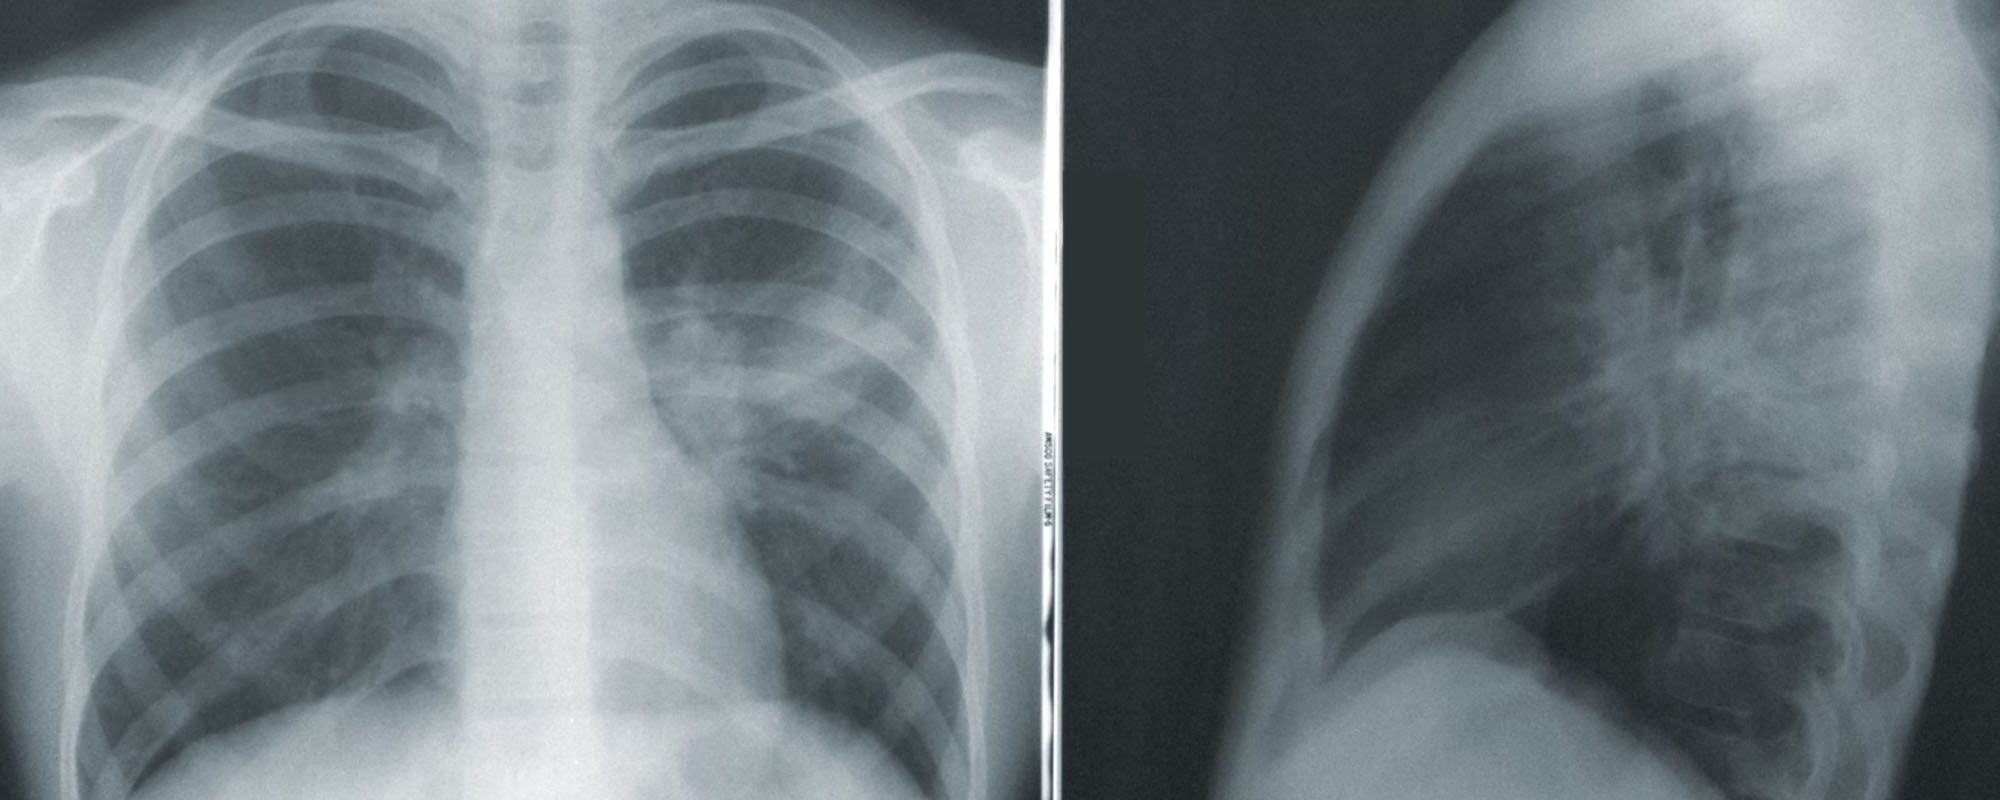

For the first time in more than a decade, the death toll from tuberculosis (TB) is rising. TB killed roughly 1.5 million people in the first year of the COVID-19 pandemic, up from 1.4 million in 2019. And researchers say COVID is to blame. COVID lockdowns, limited access to health care and patients' concerns about visiting medical clinics made TB far more deadly during the pandemic. TB patients in South Africa who were already on treatment when the pandemic hit fared well. The problem was the patients with TB who hadn't yet shown symptoms and hadn't yet sought care when the first COVID lockdown hit in March of 2020.